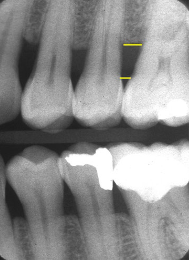

vertical bone loss M/D of #2

effects of bone loss on adjacent bone

inflammatory response to perio lesions and

more sclerotic/ radiolucent peripheral bone